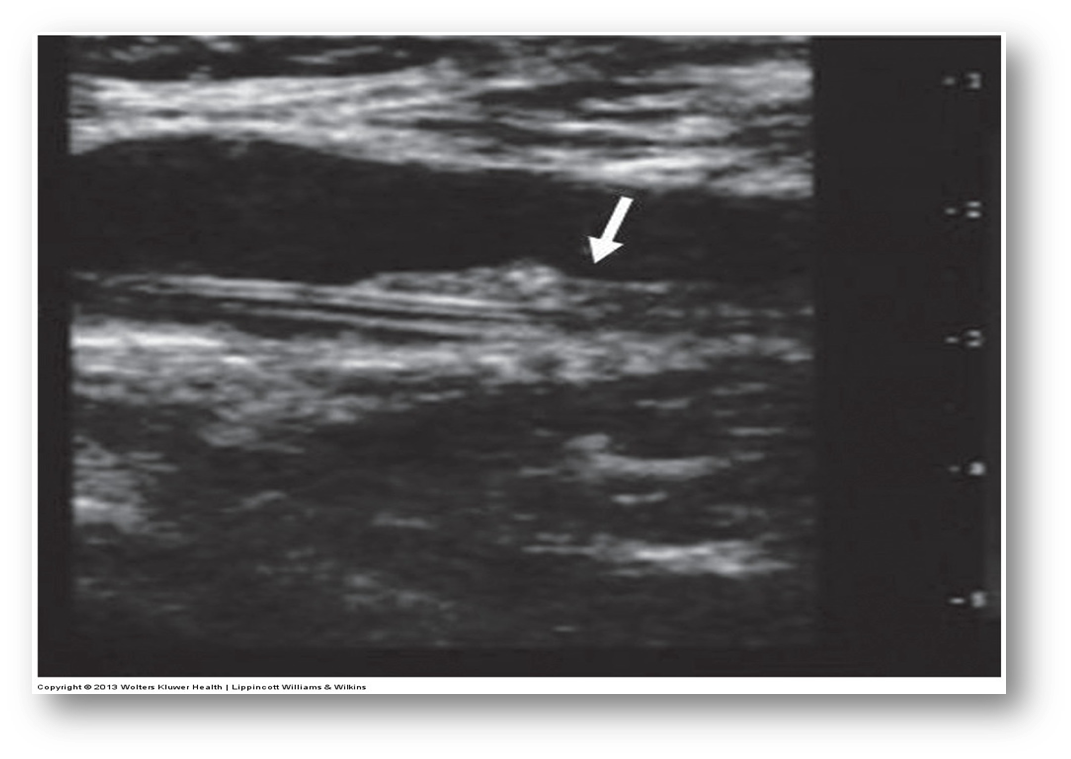

What is this image showing?

chronic blood clot

-the vein is almost completely occluded